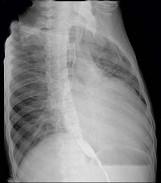

问题 56岁男性患者,劳累后心慌气促10余年,近来自觉症状加重。临床听诊,心尖区有舒张期隆隆样杂音,行胸部X检查,如图所示,你认为下列描述正确的是 ( )

选项 A、考虑三尖瓣狭窄 B、考虑二尖瓣狭窄 C、右前斜位示左心房增大,心后上缘后突压迫冲钡食管 D、左前斜位示心影向后下方突出 E、后前位示双侧肺血增多,肺动脉段隆起,左心缘出现第3弓

答案 BCDE